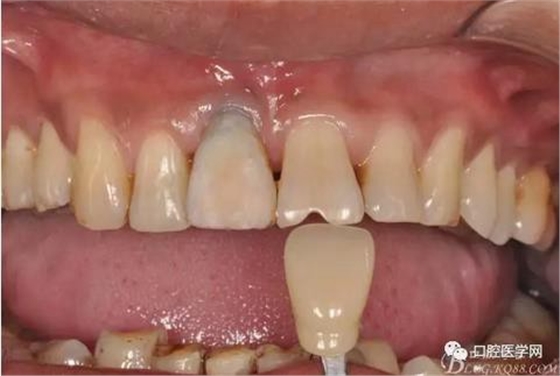

圖9 三個月后袖口形成正位照

圖10 三個月后袖口形成頜面照

圖13 比色